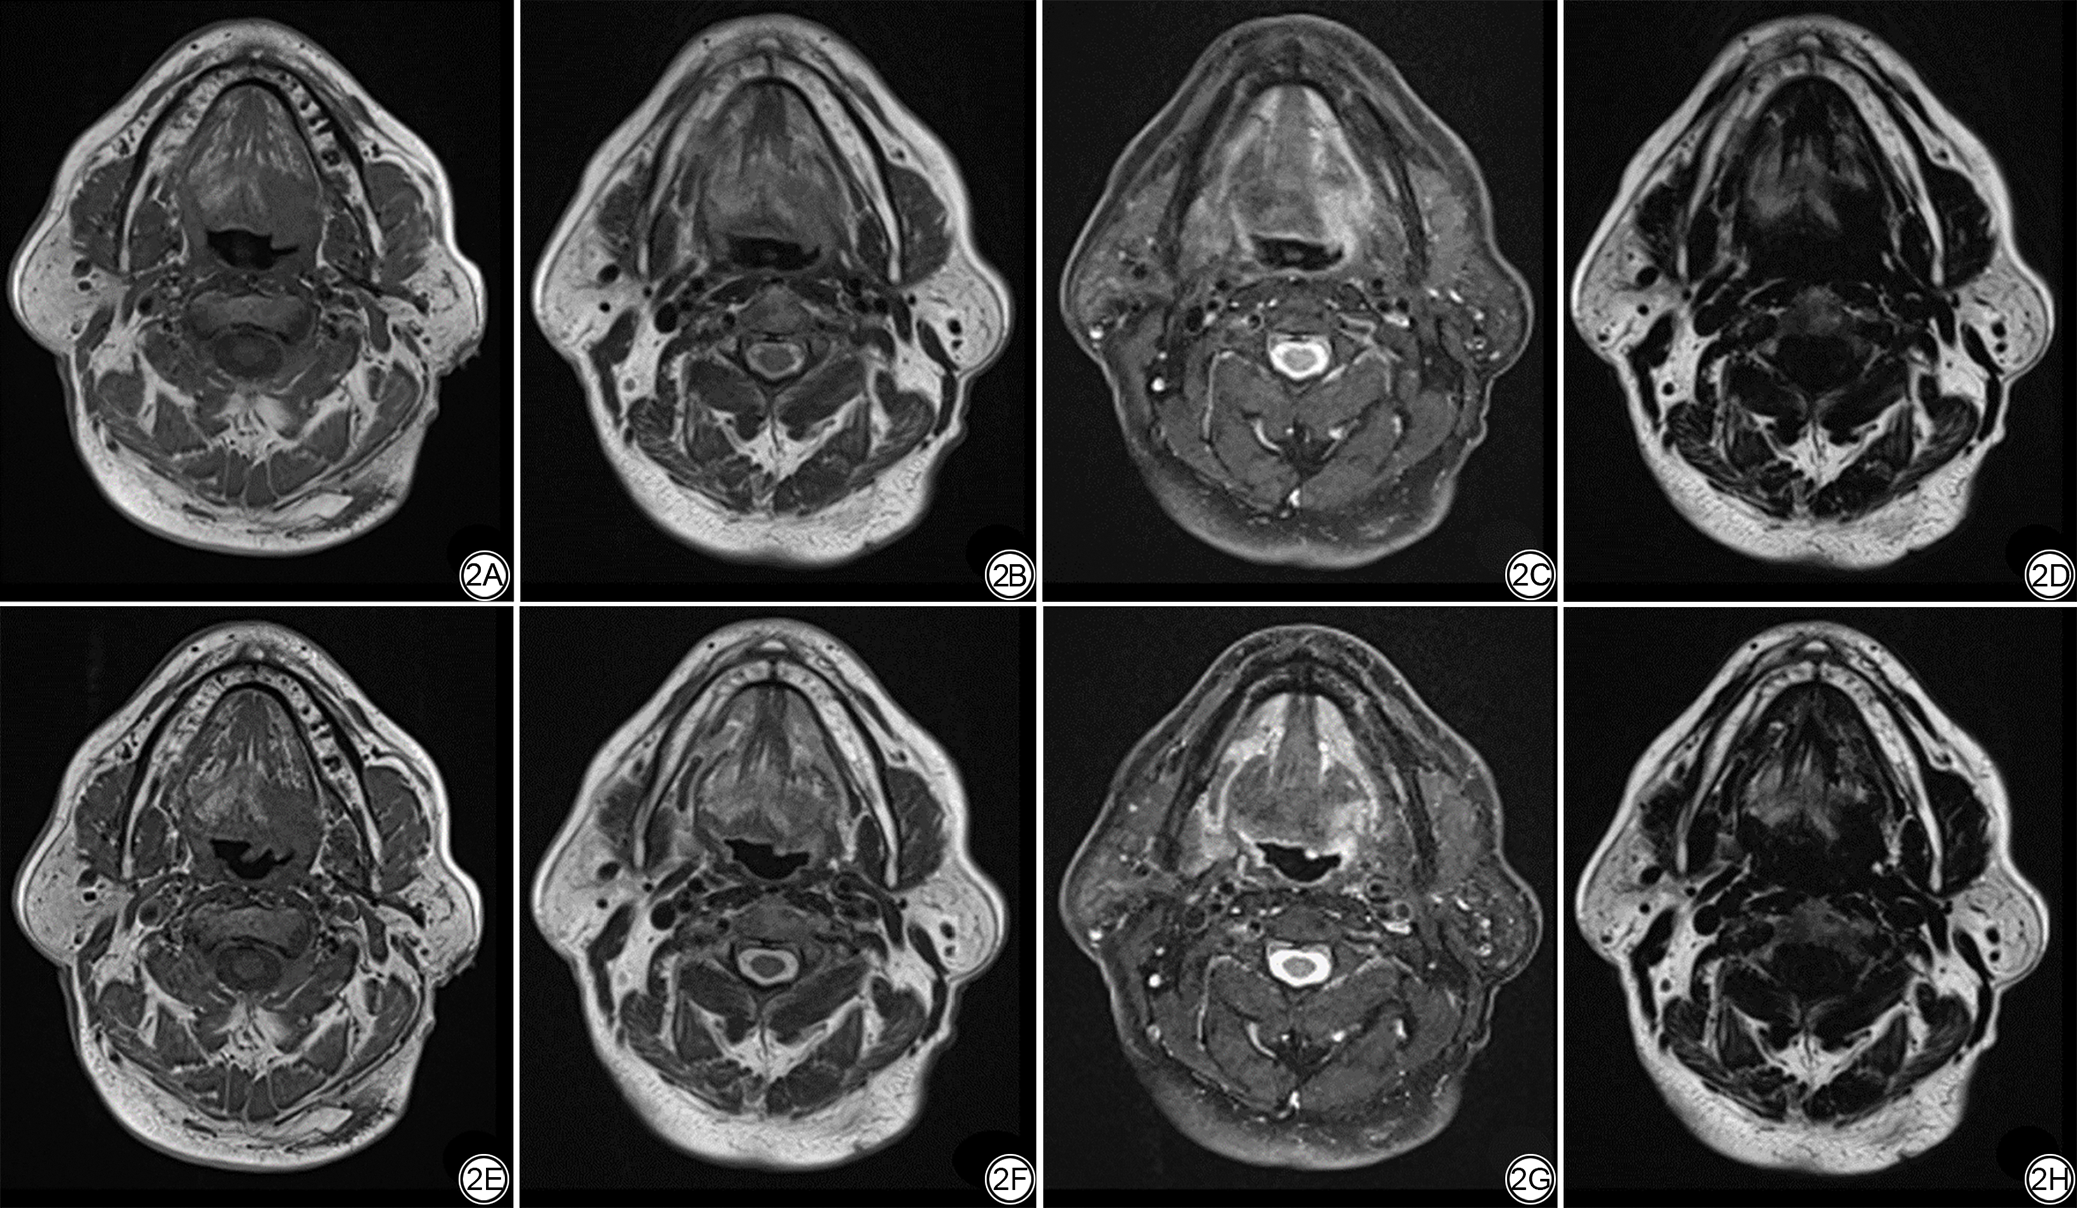

由1名具有8年经验的放射科医生在正常肌肉、脂肪和肿瘤上放置感兴趣区(region of interest, ROI)进行测量,见图1。每次测量的ROI大小及位置在同一患者的各序列间保持一致,每一个位置测量3次取平均值,计算标准T1WI、标准T2WI-Dixon序列和DL-T1WI、DL-T2WI-Dixon序列的正常肌肉、脂肪和肿瘤的信噪比(signal-to-noise ratio, SNR)及肿瘤的对比噪声比(contrast-to-noise ratio, CNR),见公式(1)~(2)。

图1  肿瘤、肌肉和脂肪ROI(红色圆圈)客观测量示意图。1A:肿瘤位置ROI(红色圆圈);1B:肌肉位置ROI(上方红色圆圈)和脂肪位置ROI(下方红色圆圈)。ROI:感兴趣区。

Fig. 1  Diagram of objective measurement in ROI (red circles) of tumor, muscle and fat. 1A: The ROI of tumor (red circle). 1B: The ROI of muscle (upper red circle) and fat (lower red circle). ROI: region of interest.